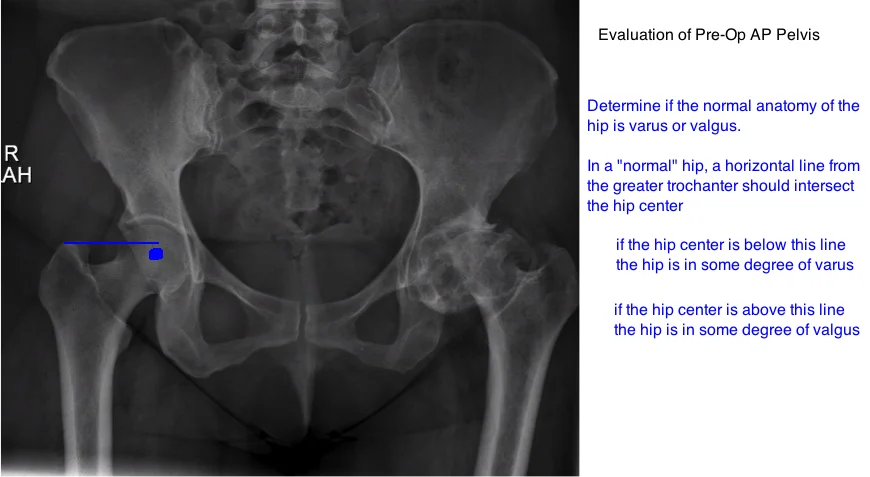

examine hip angle varus or valgus on xray

measure femoral neck angle on ap pelvis